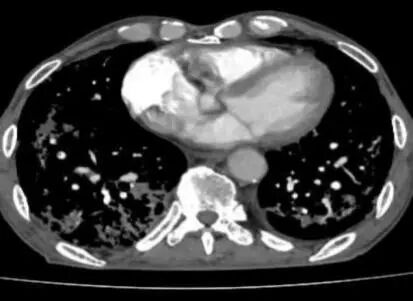

然而,病情的凶险程度远超预期,检查结果提示D-二聚体显著升高,CTPA提示右下肺动脉肺栓塞,肺部感染亦较前明显进展,病情进一步恶化。在呼吸与危重症医学科主任李芳芳带领下,团队迅速调整方案,加强抗凝与抗炎治疗。

胸部CT及CTPA